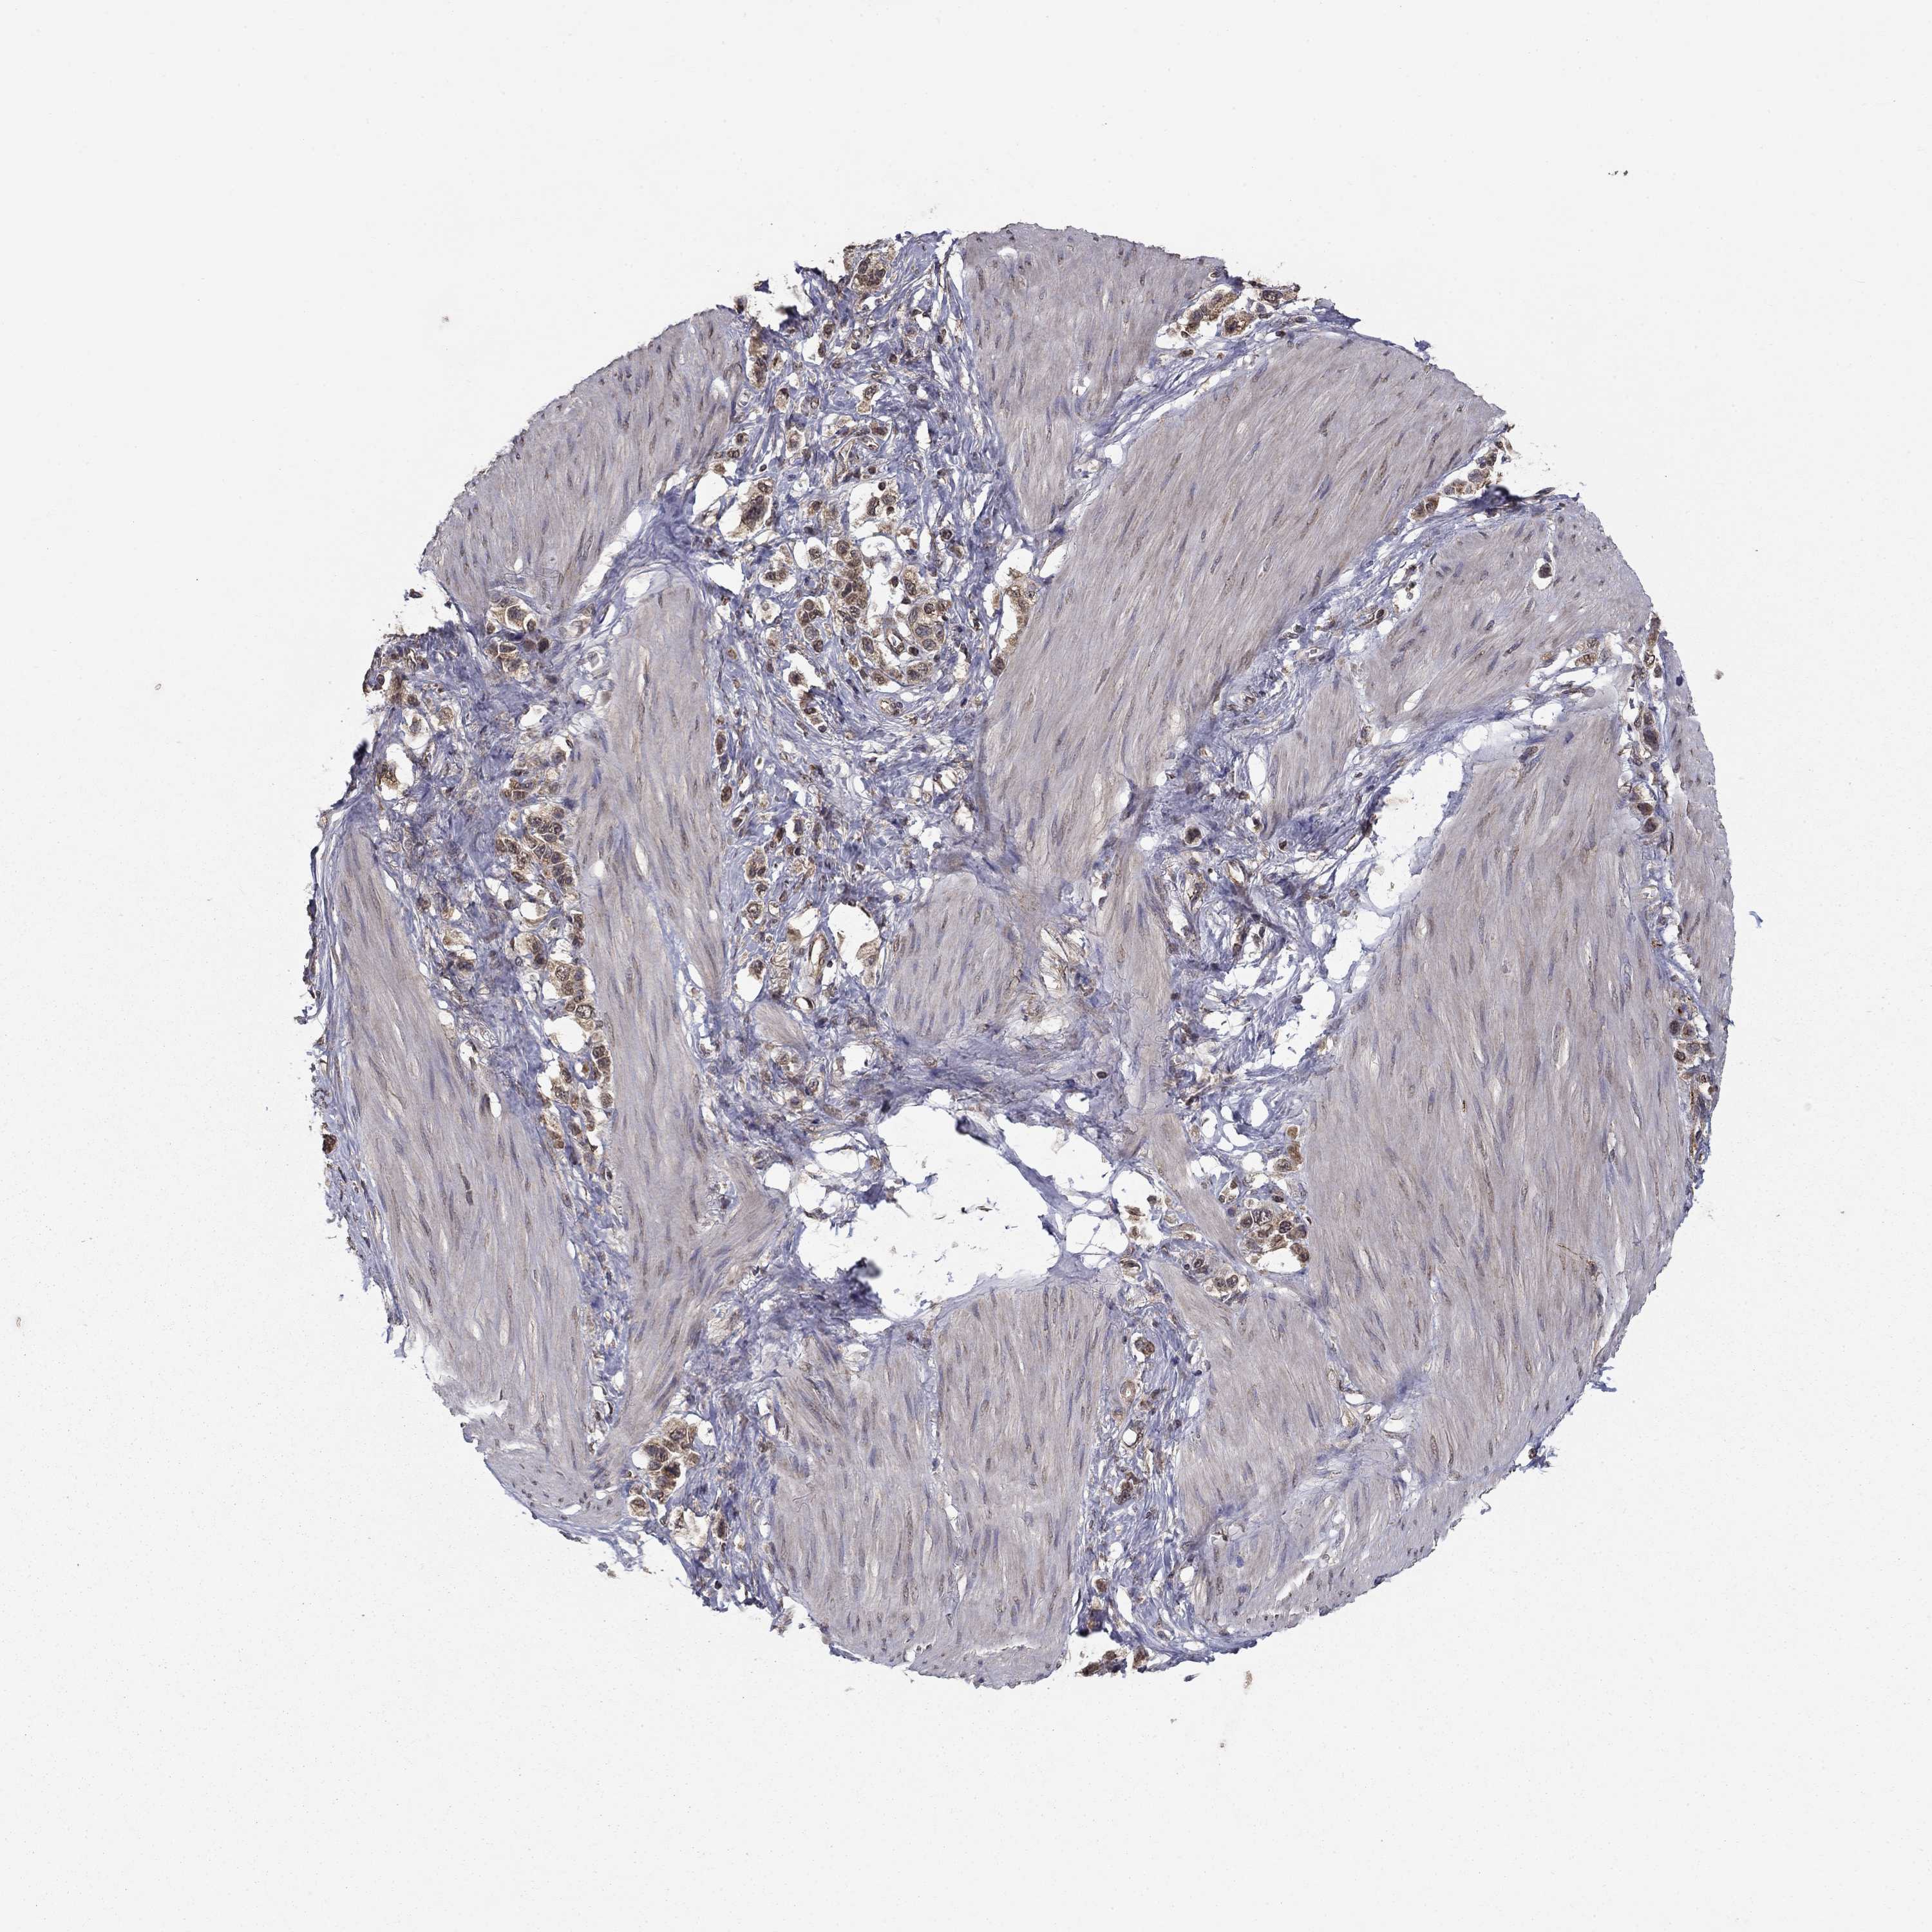

STOMACH CANCER - Protein expressioni

A mouse-over function shows sample information and annotation data. Click on an image to view it in a full screen mode. Samples can be filtered based on level of antibody staining by selecting one or several of the following categories: high, medium, low and not detected. The assay and annotation is described here.

Note that samples used for immunohistochemistry by the Human Protein Atlas do not correspond to samples in the TCGA dataset.

Antibody stainingi

Antibody staining in the annotated cell types in the current human tissue is reported as not detected, low, medium, or high, based on conventional immunohistochemistry profiling in selected tissues. This score is based on the combination of the staining intensity and fraction of stained cells.

Each image is clickable and will lead to virtual microscopy that enables deeper exploration of all samples and also displays staining intensity scores, fraction scores and subcellular localization as well as patient and tissue information for each sample.

Antibody HPA006584

Antibody HPA061679

Staining

High

Medium

Low

Not detected

Intensity

Strong

Moderate

Weak

Negative

Quantity

>75%

75%-25%

<25%

None

Location

Nuclear

Cytoplasmic/membranous

Cytoplasmic/membranous,nuclear

Adenocarcinoma, NOS

Adenocarcinoma, High grade